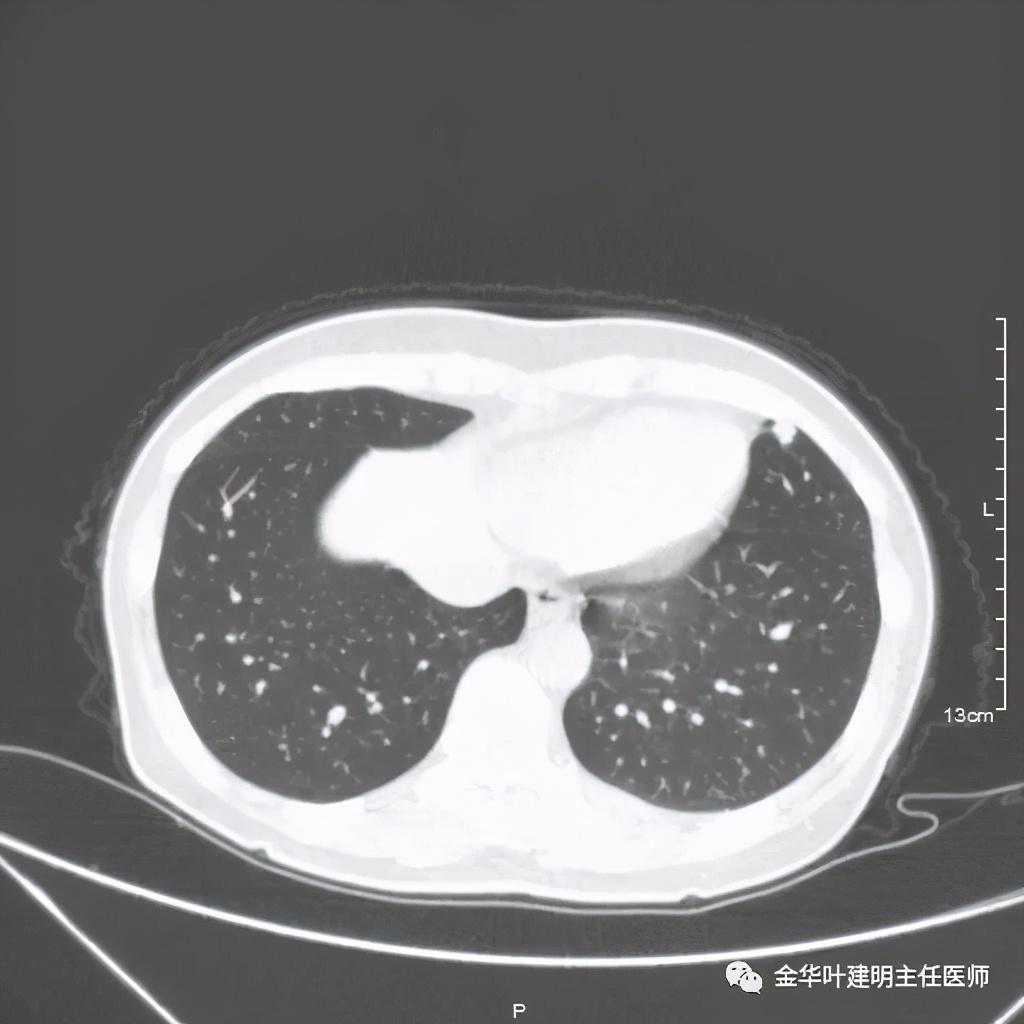

七、浸润性腺癌的其他型:

上图病例为实性,病理上实体型占80%,腺泡型占20%